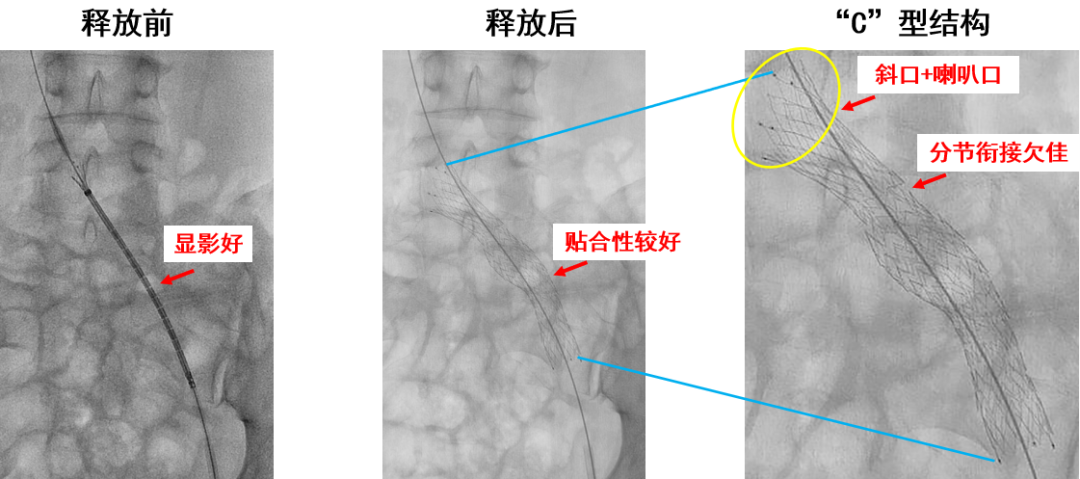

产品A:病例一(分节衔接欠佳)

产品B:病例一(支撑力及分节衔接)

近心端斜口+喇叭口,防对侧血栓形成

近端长闭环设计,支撑力强

中间开环设计,柔顺性良好

延长段支架解决了单个支架长度不够覆盖病变段的问题

近端闭环部分可完全回收并重新释放定位

开环部分支撑力待加强